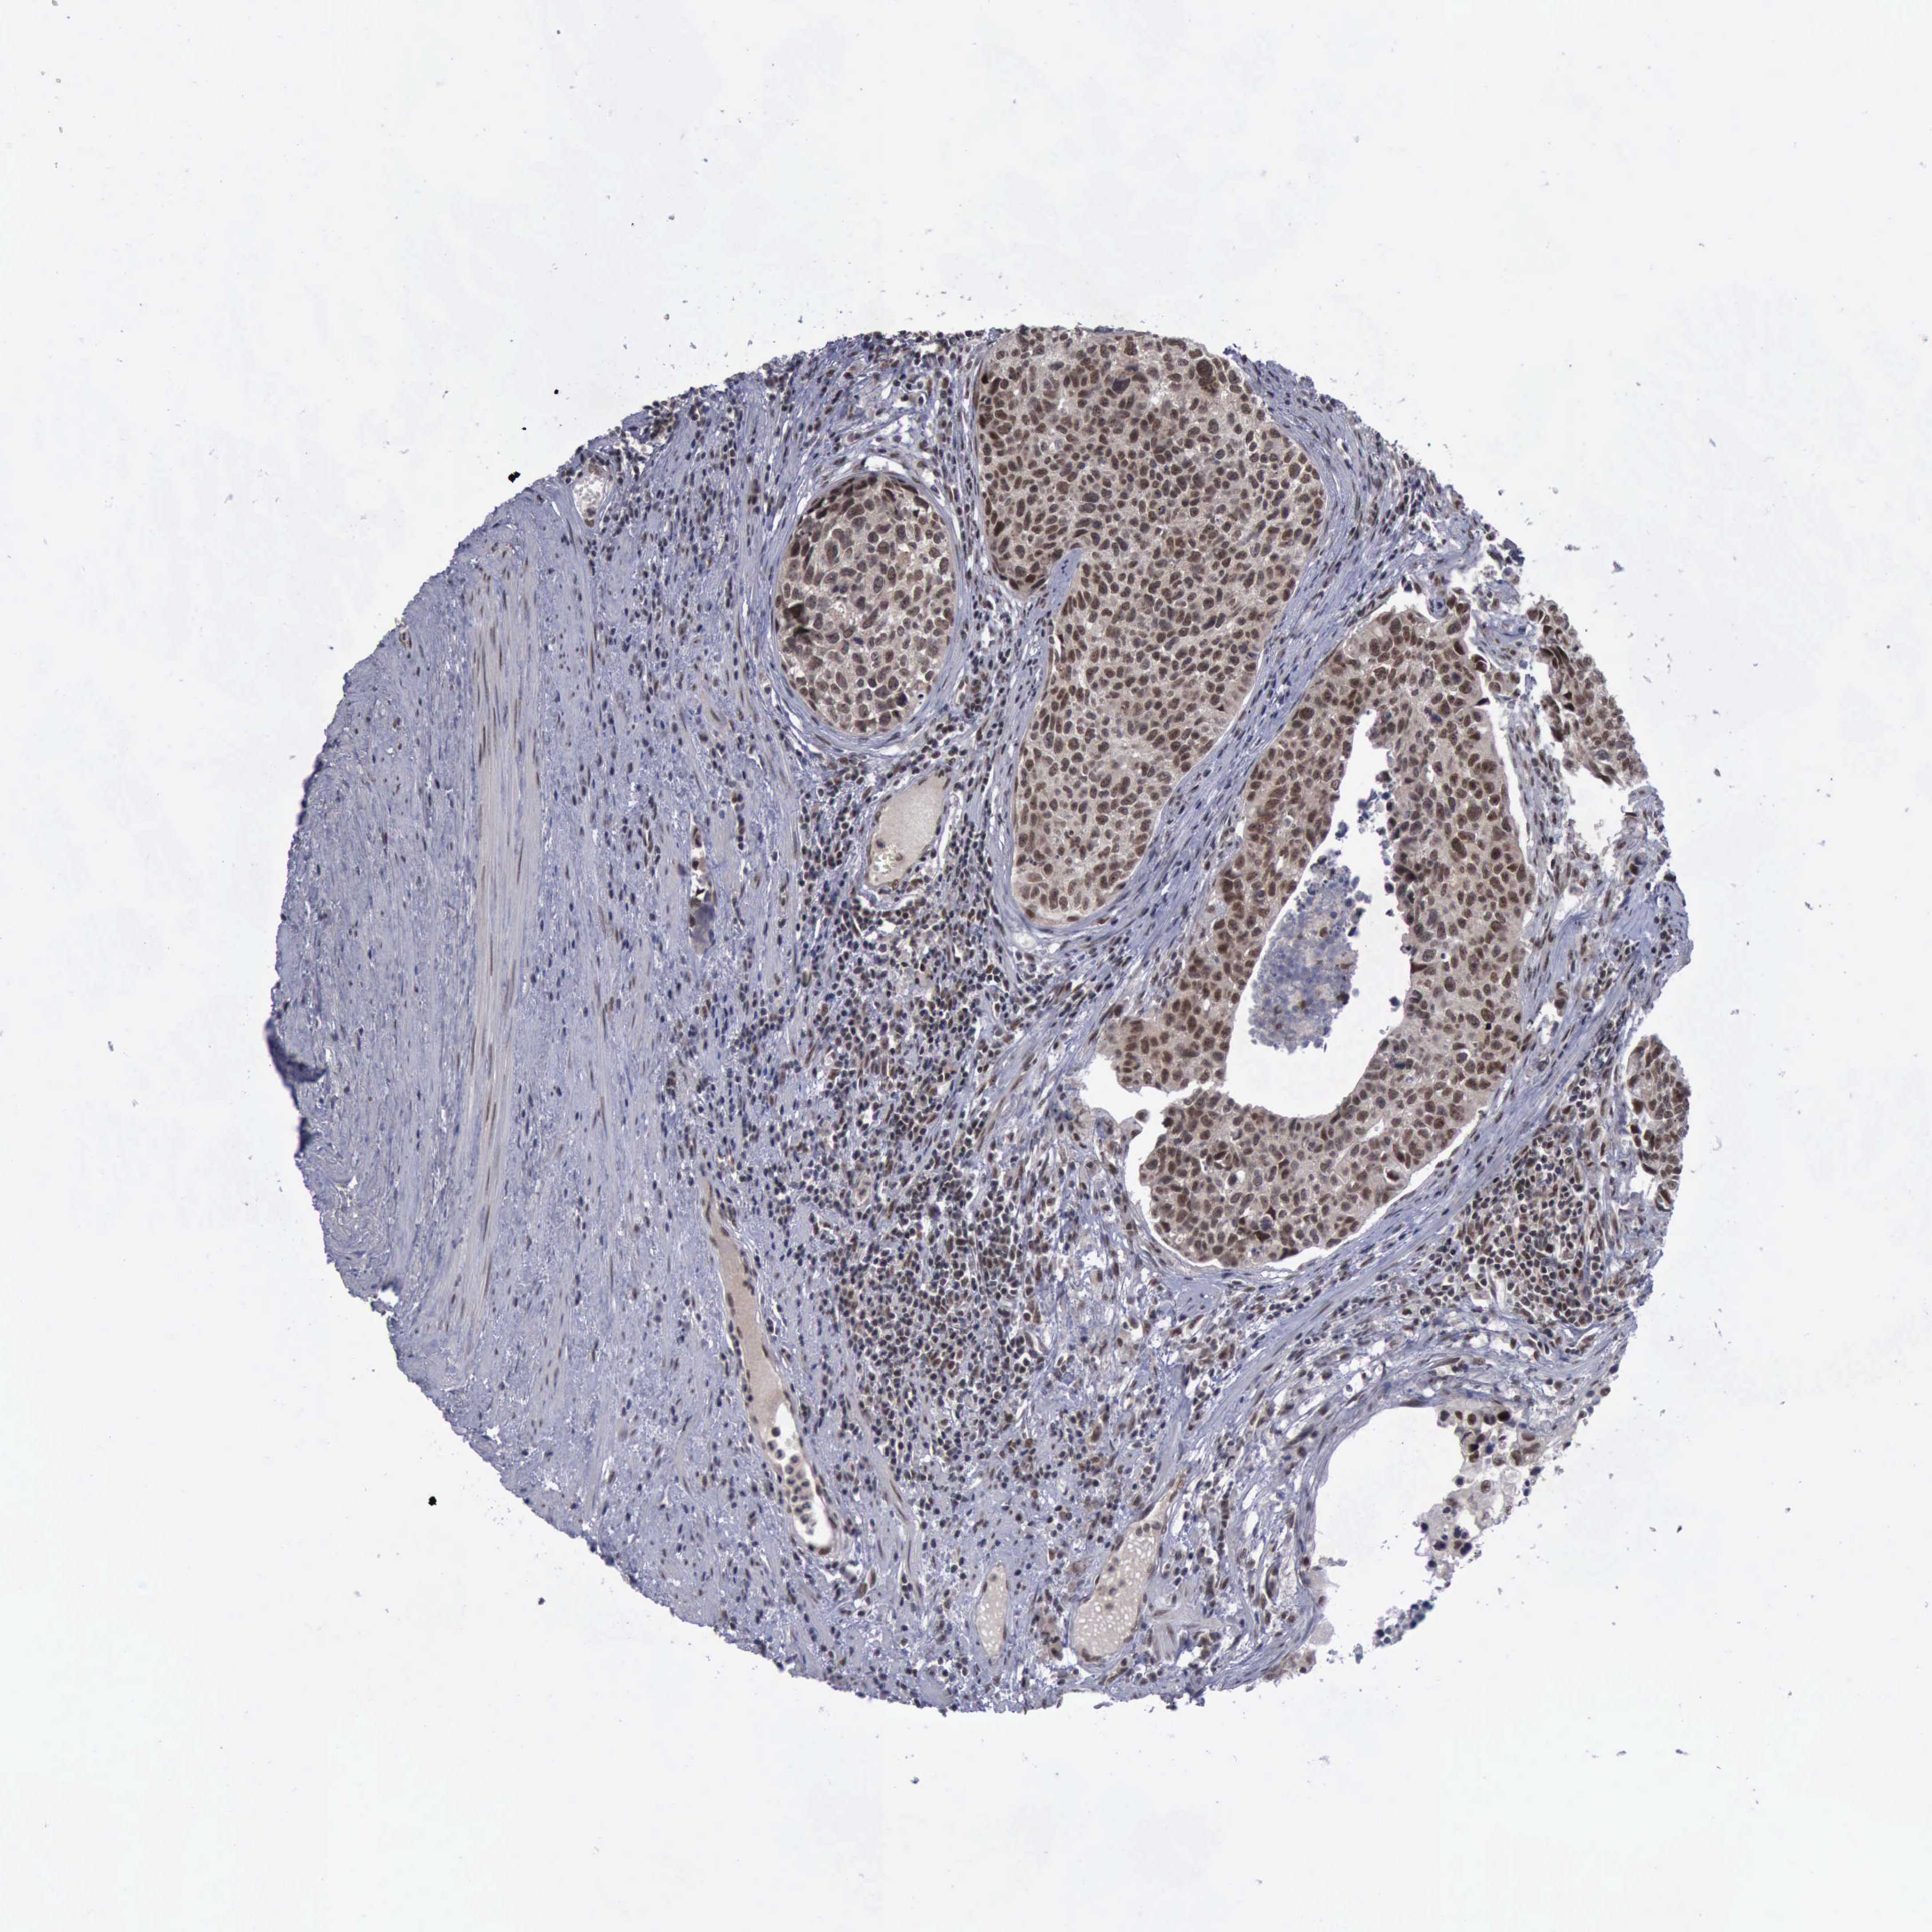

UROTHELIAL CANCER - Protein expressioni

A mouse-over function shows sample information and annotation data. Click on an image to view it in a full screen mode. Samples can be filtered based on level of antibody staining by selecting one or several of the following categories: high, medium, low and not detected. The assay and annotation is described here.

Antibody stainingi

Antibody staining in the annotated cell types in the current human tissue is reported as not detected, low, medium, or high, based on conventional immunohistochemistry profiling in selected tissues. This score is based on the combination of the staining intensity and fraction of stained cells.

Each image is clickable and will lead to virtual microscopy that enables deeper exploration of all samples and also displays staining intensity scores, fraction scores and subcellular localization as well as patient and tissue information for each sample.

Antibody CAB000102

Antibody CAB080442

Staining

High

Medium

Low

Not detected

Intensity

Strong

Moderate

Weak

Negative

Quantity

>75%

75%-25%

<25%

None

Location

Nuclear

Cytoplasmic/membranous

Cytoplasmic/membranous,nuclear

Urothelial carcinoma, Low grade